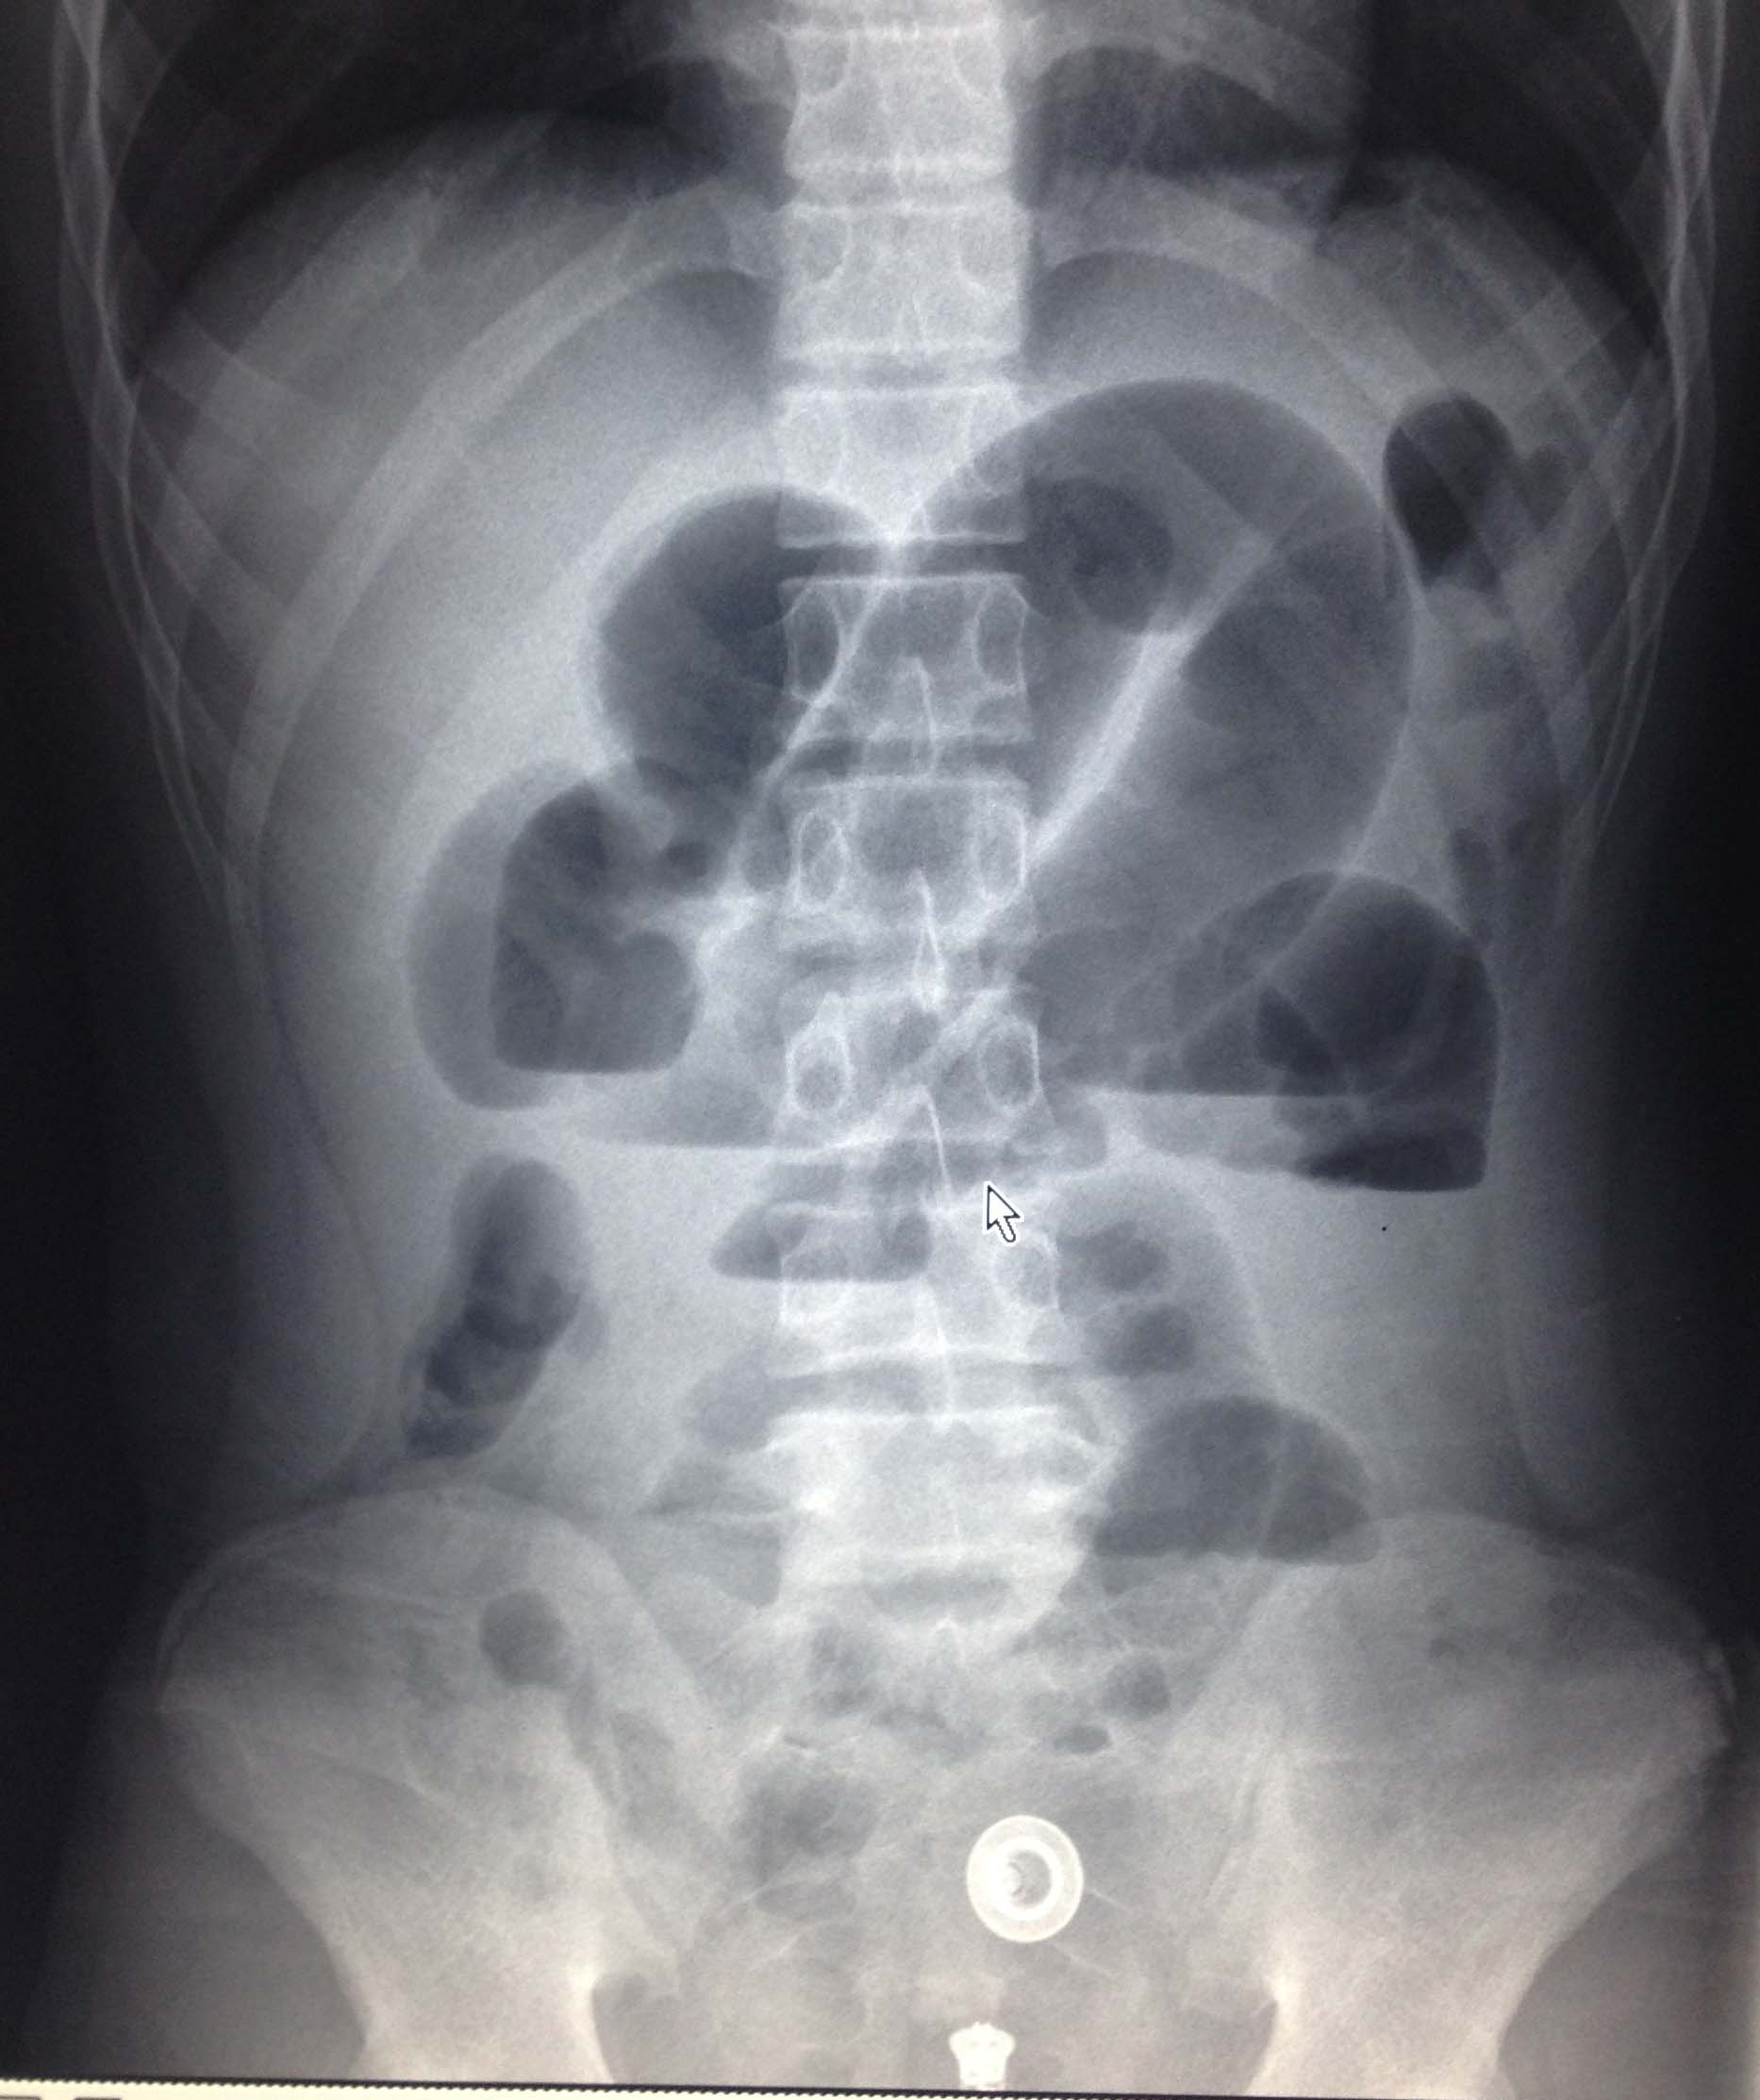

经过肠梗阻导管充分引流、减压,患者已完全康复